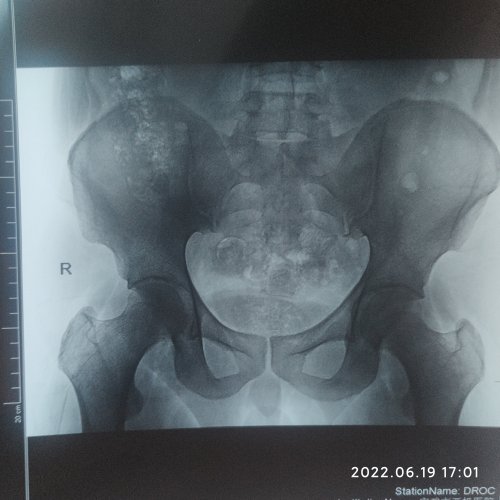

2020年春节过后开始腹股沟疼去 大腿根疼 (当时具体症状见我20年求助帖)经过村医治疗后 无效 后去省中医院外科 我描述了症状 大夫说我是慢性前列腺炎 从此走上了漫漫中医治疗之路 省中医院三个月的汤药吃了没效果后 开始看民间中医, 当地的 省上的 还有论坛里的 快手抖音上面的 中医群里面的 两年下来大概花了6W-7W 每月就是买药 看病 谈的对象也崩了 从三月份开始酸胀感觉轻了 但是有抽的感觉 我以为腰椎病 又去做腰椎检查 结果是轻微膨出 但是我总感觉大腿根不得劲 有夹肉感觉 我就在朋友圈发了一个求正骨大夫的消息 朋友连夜联系我 说他们医院有个河南正骨医院的梁医生 让我过去看看 周二我过去给我做了直腿抬高 画圈 4字实验 都不怎么疼 但就是屁股蛋快外侧深压酸胀疼的厉害 然后给我开了X光四次曝光 片子出来时候梁大夫中午下班了 让我下午来 下午我进去 梁大夫片子看了然后问我 大腿内测 腹股沟是不是也疼 这话一出来 我瞬间感觉 找对了人 髋臼撞击综合征 髋关节错位 与腰椎关系不大 屁股疼是压迫坐骨神经 建议我住院理疗 第一期治疗十五天先恢复脊椎跟骨盆 完了休息一月再住一次把髋臼拉出间隙就好了 今天是出院第三天 天天项目是 早上开始挂牵引30分钟 敷药半个小时 中频半个小时 熏蒸半个小时 下午牵引 中频 针灸 还有一周汤药一个疗程下来花了1700 现在酸胀是没有了 大腿根疼的很轻微了 可能是正骨还是腰带穿的太久压迫哪里 昨天开始左小腿肌肉最下面不得劲了 但是真的是看到希望了 真的折腾的我真的想自挂东南枝去 健脾的 升阳的 补肾的 疏肝解郁的 活血的 祛湿 就没停过 啥作用都没有 舌头改淡白还是淡白 齿痕该有还是有 真的感觉跟药倒沟里去一样

2020年春节过后开始腹股沟疼去 大腿根疼 (当时具体症状见我20年求助帖)经过村医治疗后 无效 后去省中医院外科 我描述了症状 大夫说我是慢性前列腺炎 从此走上了漫漫中医治疗之路 省中医院三个月的汤药吃了没效果后 开始看民间中医, 当地的 省上的 还有论坛里的 快手抖音上面的 中医群里面的 两年下来大概花了6W-7W 每月就是买药 看病 谈的对象也崩了 从三月份开始酸胀感觉轻了 但是有抽的感觉 我以为腰椎病 又去做腰椎检查 结果是轻微膨出 但是我总感觉大腿根不得劲 有夹肉感觉 我就在朋友圈发了一个求正骨大夫的消息 朋友连夜联系我 说他们医院有个河南正骨医院的梁医生 让我过去看看 周二我过去给我做了直腿抬高 画圈 4字实验 都不怎么疼 但就是屁股蛋快外侧深压酸胀疼的厉害 然后给我开了X光四次曝光 片子出来时候梁大夫中午下班了 让我下午来 下午我进去 梁大夫片子看了然后问我 大腿内测 腹股沟是不是也疼 这话一出来 我瞬间感觉 找对了人 髋臼撞击综合征 髋关节错位 与腰椎关系不大 屁股疼是压迫坐骨神经 建议我住院理疗 第一期治疗十五天先恢复脊椎跟骨盆 完了休息一月再住一次把髋臼拉出间隙就好了 今天是出院第三天 天天项目是 早上开始挂牵引30分钟 敷药半个小时 中频半个小时 熏蒸半个小时 下午牵引 中频 针灸 还有一周汤药一个疗程下来花了1700 现在酸胀是没有了 大腿根疼的很轻微了 可能是正骨还是腰带穿的太久压迫哪里 昨天开始左小腿肌肉最下面不得劲了 但是真的是看到希望了 真的折腾的我真的想自挂东南枝去 健脾的 升阳的 补肾的 疏肝解郁的 活血的 祛湿 就没停过 啥作用都没有 舌头改淡白还是淡白 齿痕该有还是有 真的感觉跟药倒沟里去一样